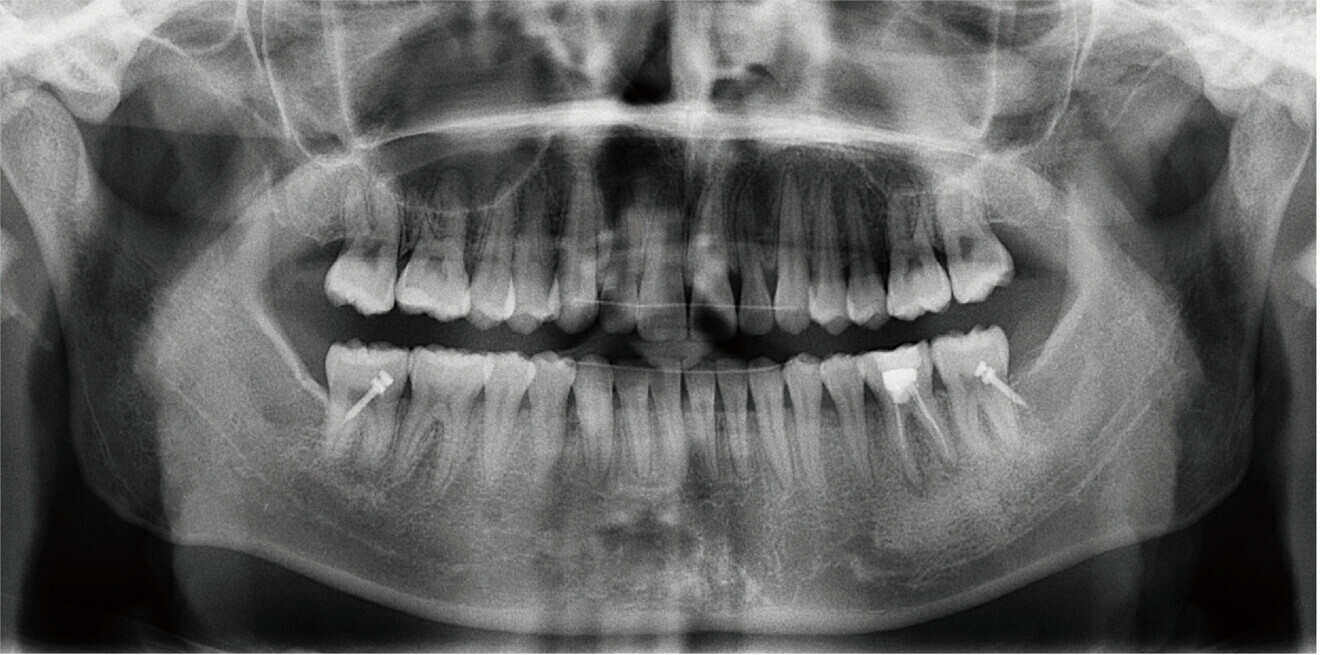

Fig. 5b: Dental panoramic tomogram taken after completion of mandibular repositioning therapy.